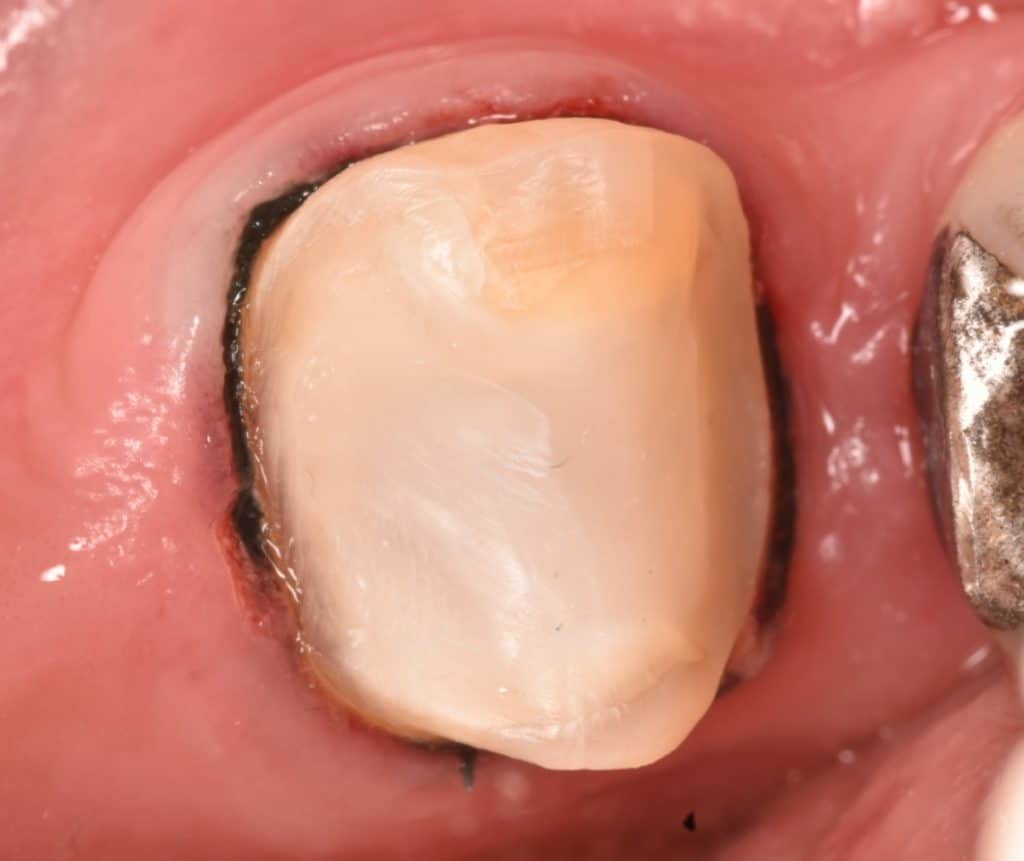

After amalgam removal the cavity was very large and destructive MOD cavity

In the second visit isolation with rubberdam ,all caries in the proximal sides removed , the margin will elevated